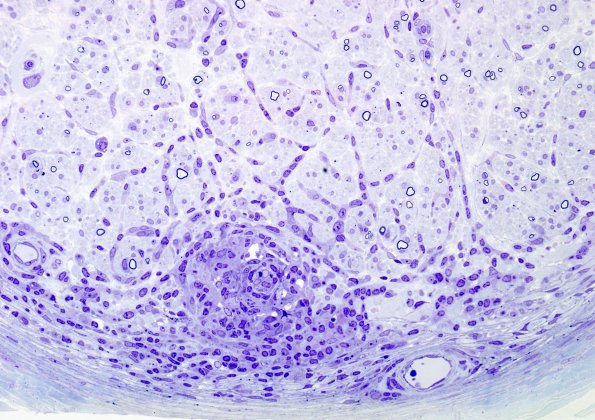

1B1B Leprosy, tuberculoid (Case 1) Plastic 1

Higher magnification of a granuloma in 1B1A. (Plastic section)